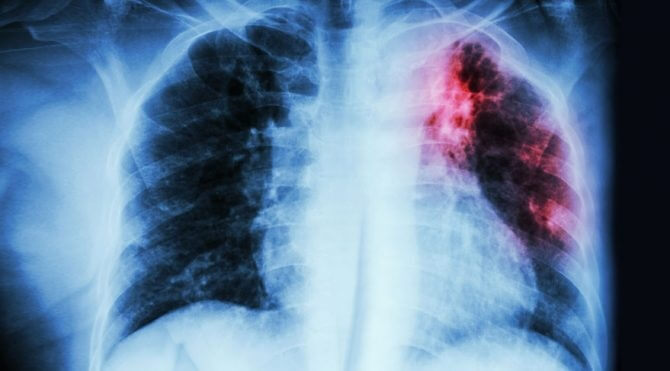

Dünya Sağlık Örgütü (DSÖ), tüberküloz nedeniyle her yıl 1,5 milyondan fazla kişinin yaşamını yitirdiğini açıkladı.

Ghebreyesus, bu hastalığı sonlandırmanın DSÖ’nün öncelikleri arasında bulunduğunu vurgulayarak, “Tüberküloz her yıl 1,5 milyondan fazla kişiyi öldürüyor ve milyonlarca kişiyi daha etkiliyor.” bilgisini paylaştı.

Covid-19 ile mücadele nedeniyle tüberküloz tedavilerinin aksadığını kaydeden Ghebreyesus, “DSÖ’nün verilerine göre sağlık hizmetlerindeki aksamalardan dolayı yıllık tüberküloz ölümleri son 10 yılda ilk defa artış gösterdi.” ifadelerini kullandı.

Ghebreyesus, son yıllarda Covid-19 nedeniyle tüberküloz ile mücadeleye aktarılan bütçenin de azaldığının altını çizerek, tüberküloz teşhis, tedavi ve önleme hizmetlerine küresel çapta yapılan harcamaların 2019’da 5,8 milyar ABD doları iken 2021’de 5,3 milyar dolara düştüğü bilgisini paylaştı.